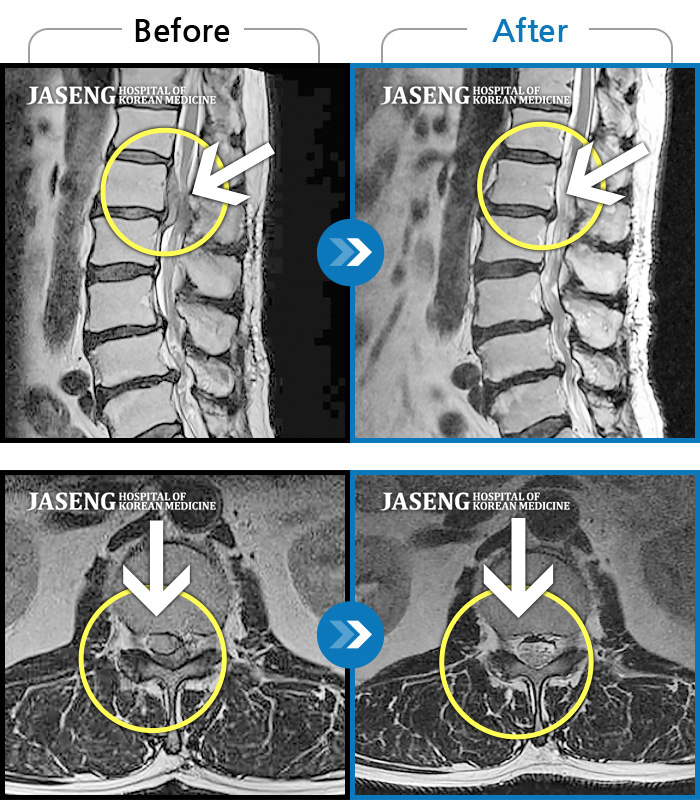

Before

After

환자에게 사전 동의를 받아 동일 조건에서 촬영되었습니다.

개인에 따라 치료 후 부작용이 발생할 수 있으니 의료진과 상담 후 치료를 진행하시기 바랍니다.

우측 허리 골반 통증과 우측 다리 방사통, 우측 다리 감각 둔화

허리 아프고 보행시 우측 다리 통증